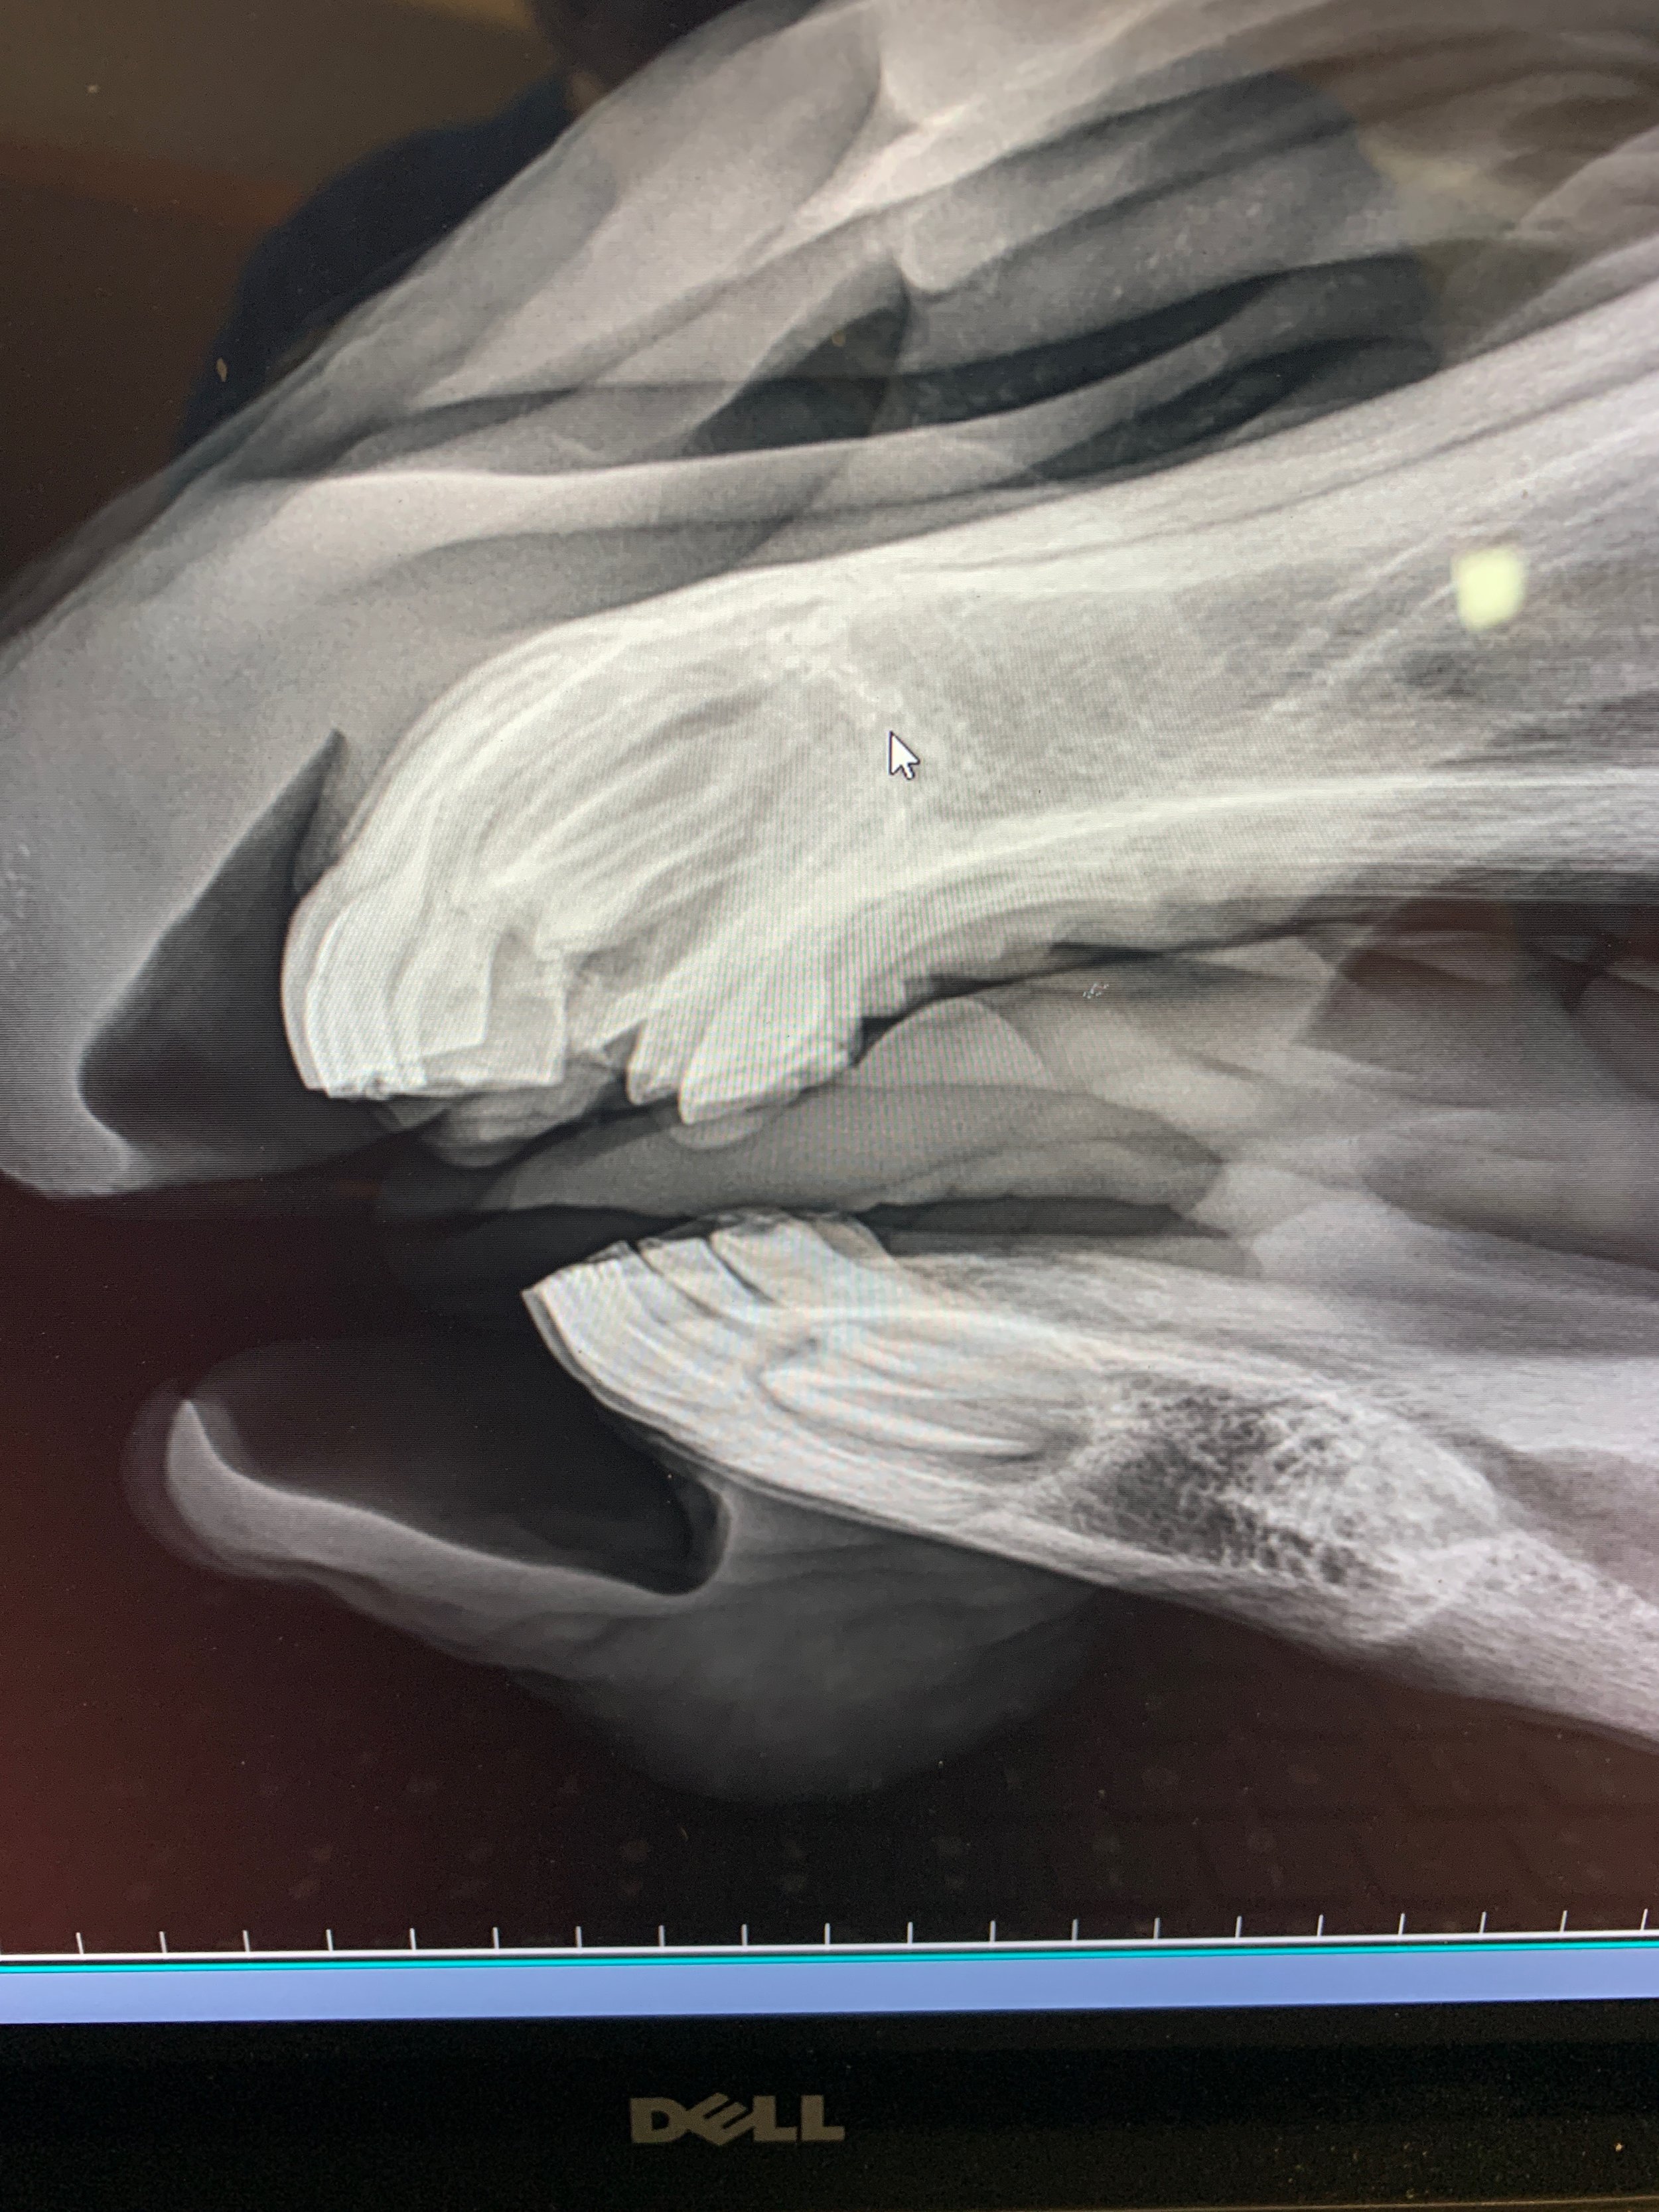

At Oakhurst, our work spans far beyond the walls of a traditional equine practice. This slideshow offers a glimpse into the many facets of what we do—from caring for sport horses, racehorses, and beloved companions to supporting mare and stallion owners through comprehensive reproductive services. You’ll see how our team blends advanced medical care with hands-on client education, podiatry services, and student teaching, all with a focus on practical, forward-thinking equine medicine. We also provide a range of surgical procedures that don’t require a full operating room, bringing efficient, high-quality care directly to the horses who need it.